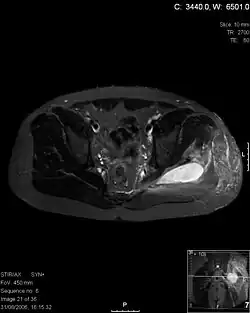

| Transverse T2 magnetic resonance imaging section through the hip region showing abscess collection in a patient with pyomyositis. | |

Coronal T2 weighted fat suppressed image showing a multiloculated fluid collection in the left gluteal musculature due to tropical pyomositis in a 12-year-old boy.